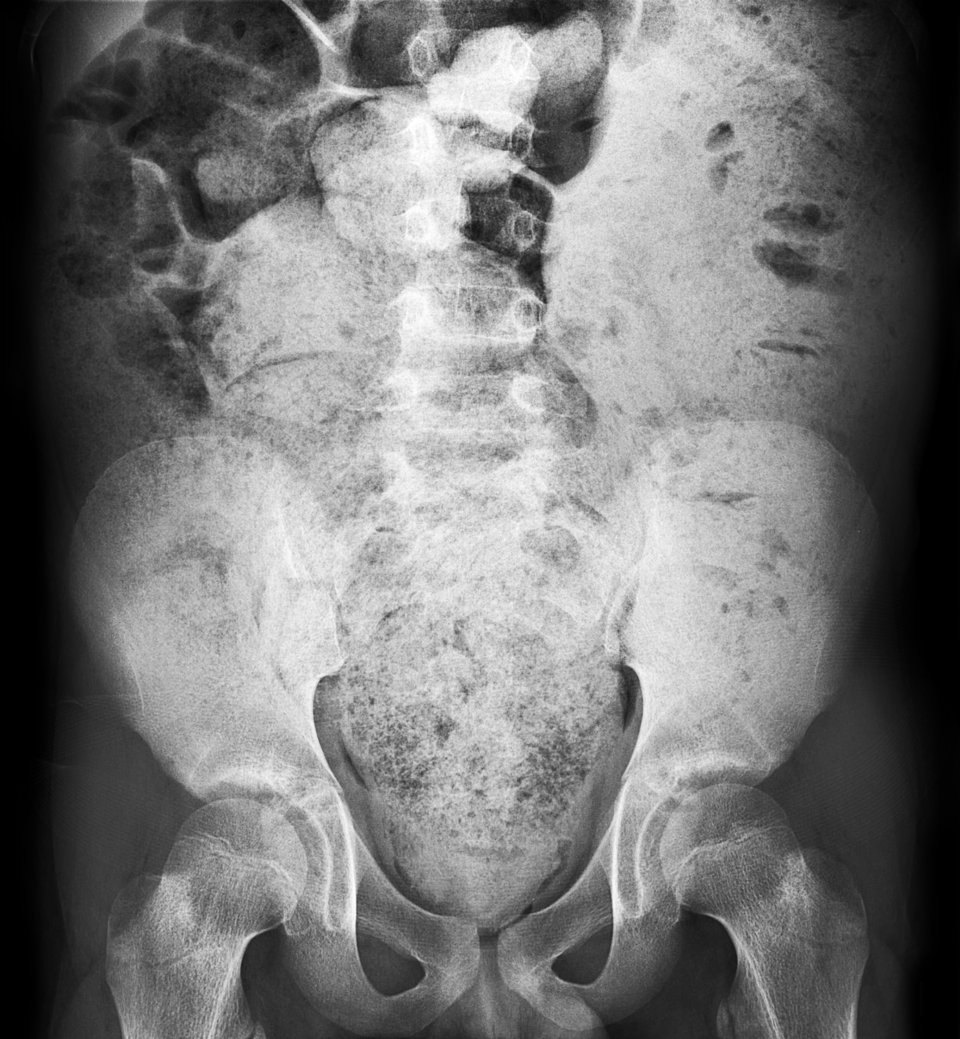

Den meisten Fällen von Darmverschluss in der Primär- oder Notfallversorgung liegt eine mechanisch bedingte Obstruktion zugrunde. Den meisten Fällen von Darmverschluss in der Primär- oder Notfallversorgung liegt eine mechanisch bedingte Obstruktion zugrunde. © iStock/vittaya25

Den meisten Fällen von Darmverschluss in der Primär- oder Notfallversorgung liegt eine mechanisch durch Blockade oder Verdrehen bedingte Obstruktion zugrunde, selten ein paralytischer Ileus. Intraluminale Blockaden durch Stuhlimpaktion machen weniger als 10 % der Ursachen von akuten Darmverschlüssen aus. Den größten Anteil stellen extraluminale wie Adhäsionen (60 %) und obstruierte Hernien (12 %).

Prall mit Fäzes gefüllter Dickdarm im Rahmen einer Obstruktion. Prall mit Fäzes gefüllter Dickdarm im Rahmen einer Obstruktion. © Science Photo Library